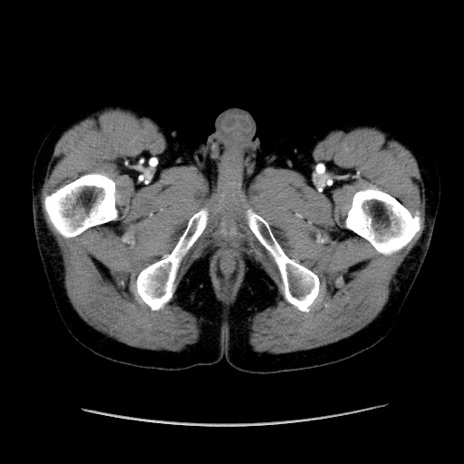

症例37(横断像)

【症例】40歳代 男性

【主訴】腹痛

【現病歴】4時間ほど前に電車に乗車中に臍部上より腹痛出現。徐々に増悪し起立困難となり、救急外来受診。生ものは数日食べていない。今朝お雑煮を食べた。

【身体所見】BT 36.8℃、BP 117/84mmHg、HR 91/min、SpO2 97%、苦悶様、腹部:臍上部広範囲圧痛あり、反跳痛±

【データ】WBC 8100、CRP 0.03